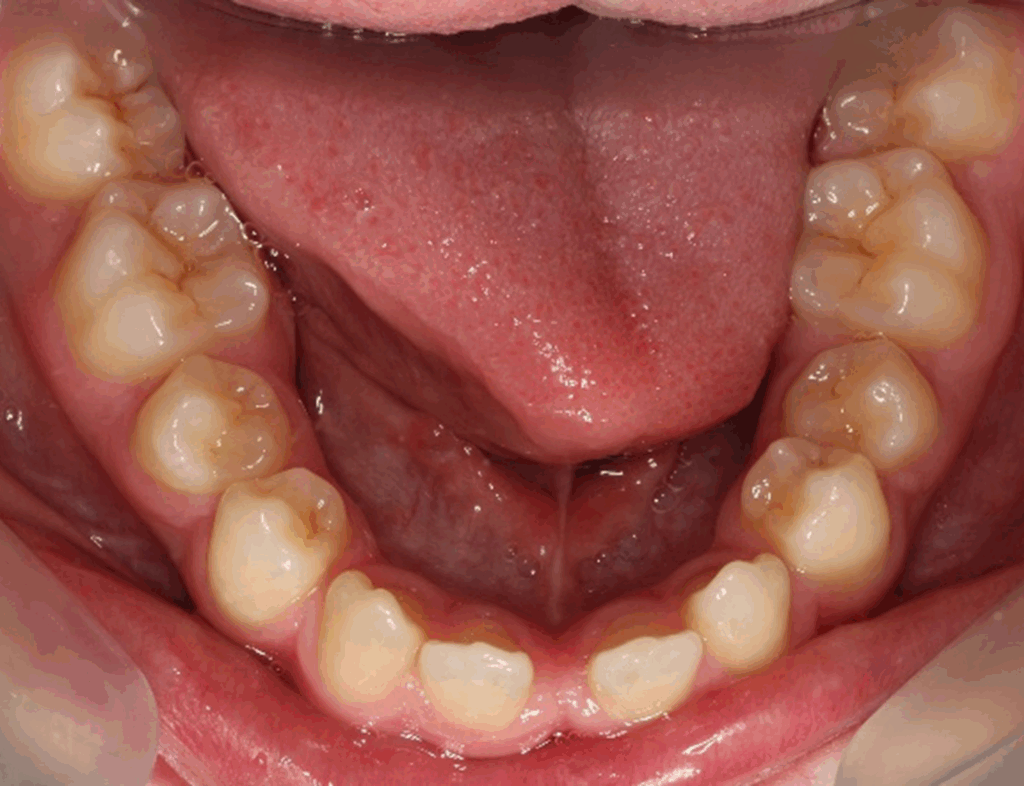

Skeletal Class II due to mandibular retrognathia, proclination of maxillary incisors, narrow arch creating a V-shaped arch, agenesis of 12, 31, 41, hyperdivergent facial pattern, moderate deep bite (2 mm), increased overjet (9 mm), asymmetric canine and molar Class II due to mandibular deviation to the left, maxillary midline deviation related to agenesis of 12, distal rotation of 35 and 45, and pronounced lower curve of Spee.

Lower arch: 31 active aligners

Incisor intrusion using frog staging

Vertical attachments on lower incisors for improved tipping control

Space opening for 31 and 41

Elastics protocol

Class II elastics: 4.5 oz, 14 hours/day

Hooks on 13 and 23, button cut-outs on lower molars